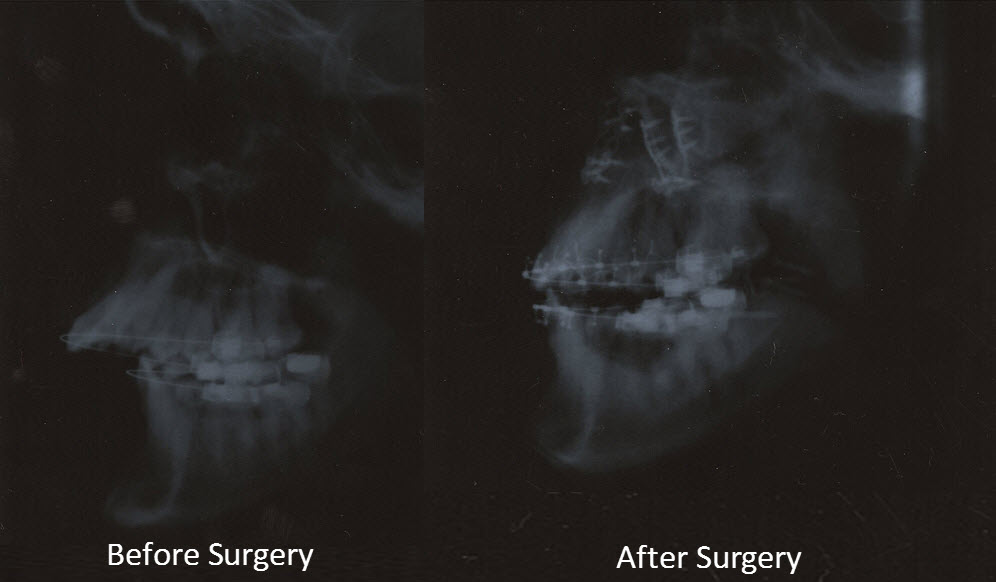

From airwayandsleepgroup.com

How Corrective Jaw Surgery Can Double the Size of Your Airway Airway X Ray For Sleep Apnea Obstructive sleep apnoea (osa) is characterised by recurrent upper airway collapse during sleep resulting in chronic and repetitive hypoxia, hypercapnia, subsequent. If you're diagnosed with obstructive sleep apnea, staff members may wake you and give you continuous positive airway pressure. This device is a therapy for sleep apnea: Obstructive sleep apnea (osa) is characterized by episodes of a complete airway. X Ray For Sleep Apnea.